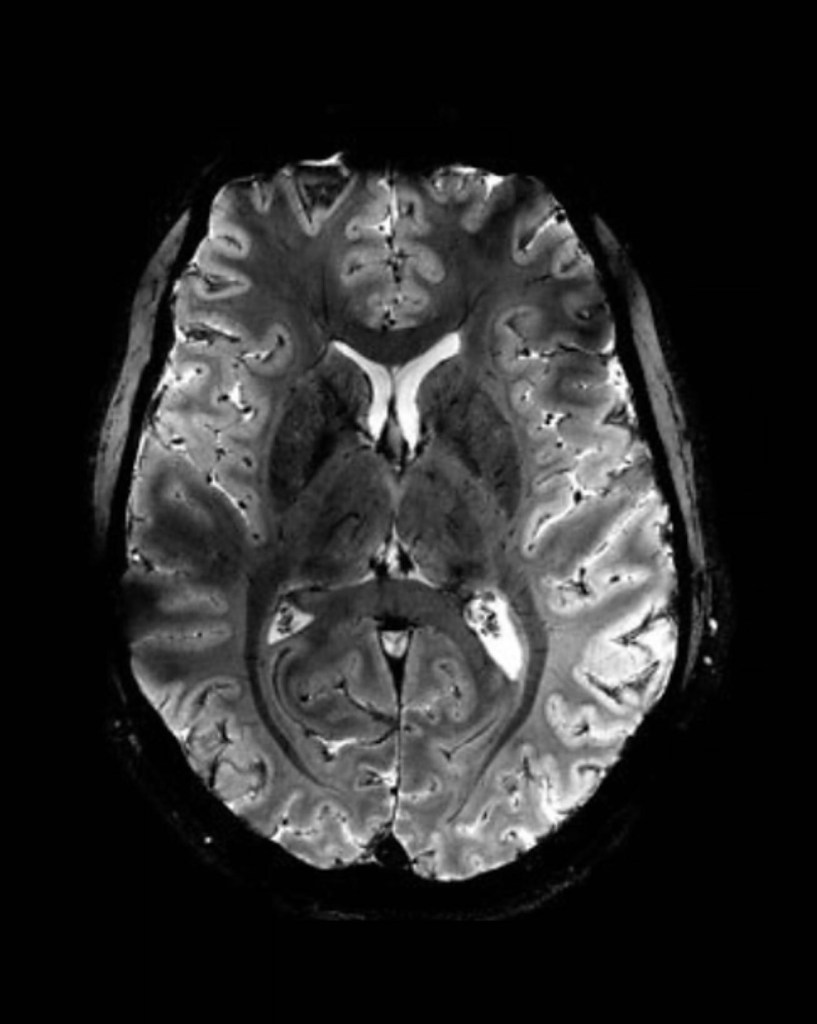

En un estreno mundial, los investigadores de la Comisión de Energía Atómica (CEA) de Francia revelaron este martes una serie de imágenes ‘in vivo’ del cerebro humano, adquiridas con la máquina de resonancia magnética más poderosa del mundo. La Iseult, que cuenta con un inigualable campo magnético de 11,7 teslas y fue construida en un esfuerzo de dos décadas, ha captado el cerebro vivo con una claridad sin precedentes.

Las más notables imágenes anatómicas del cerebro nunca antes obtenidas se tomaron en apenas cuatro minutos. Los expertos señalan que su resolución es impresionante para un lapso temporal de adquisición tan corto. Se logró una resolución en el plano de 0,2 mm y grosor de corte de 1 mm, lo que representa un volumen equivalente a unos pocos miles de neuronas.

En comparación, la misma calidad de imagen requeriría horas con los escáneres de resonancia magnética actualmente disponibles (de 1,5 o 3 teslas). Esto no es realista en la práctica, ya que los pacientes no se sentirían cómodos y cualquier movimiento haría que la imagen se vea «borrosa».